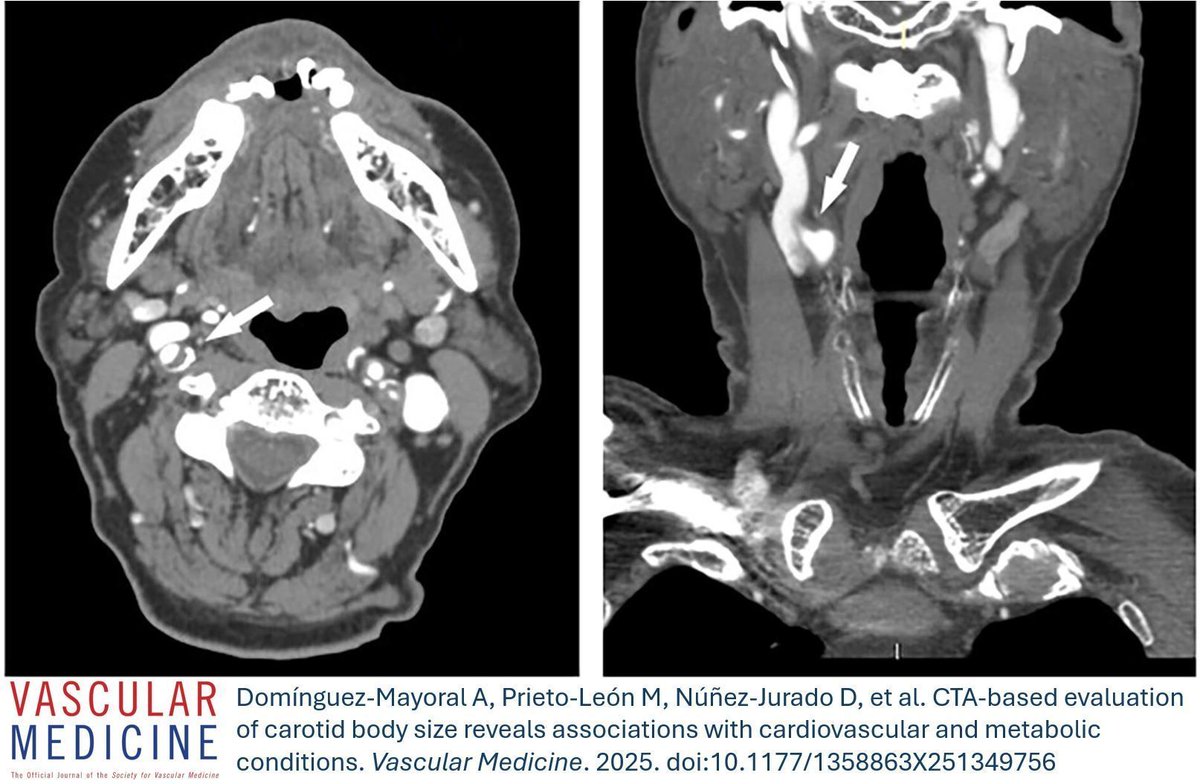

From the latest issue: Tanda and colleagues share a unique case of a giant 'Kommerell' diverticulum in a bovine arch resulting in dysphonia and dysphagia. https://t.co/qpWYEciUeW

#Aorta